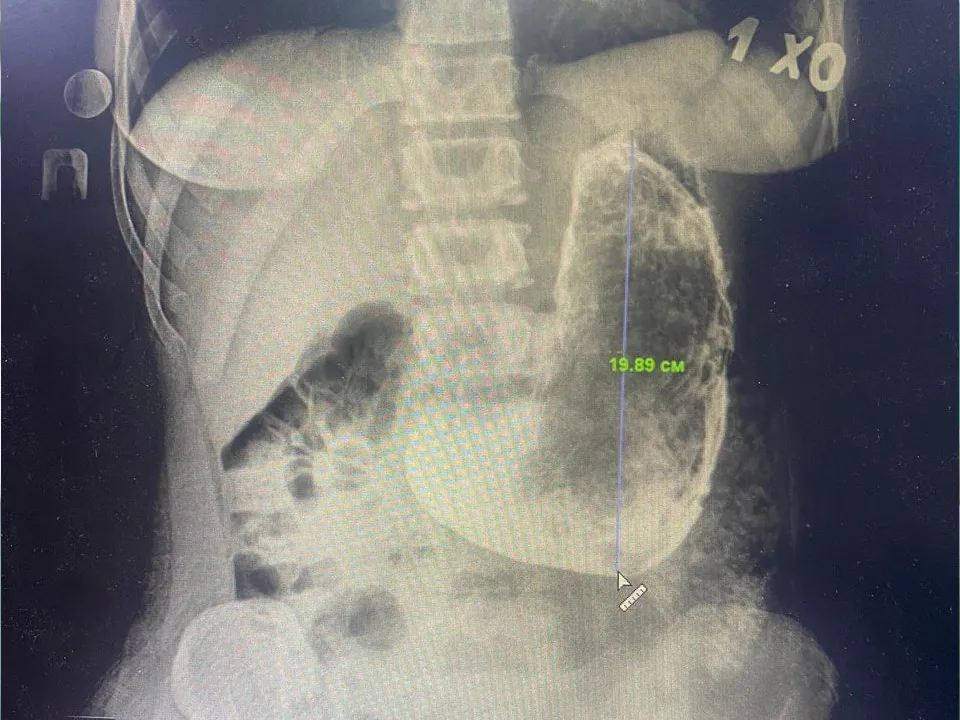

Когда боль стала невыносимой, девушка обратилась за медицинской помощью в больницу Красногорска. Как сообщили в Министерстве здравоохранения Московской области на своей странице Вконтакте, обследование выявило в ее желудке инородное тело размером 20×15 сантиметров.

Заведующий хирургическим отделением Красногорской больницы Николай Мурашов сообщил, что из-за больших размеров и плотной консистенции образования было принято решение провести операцию.